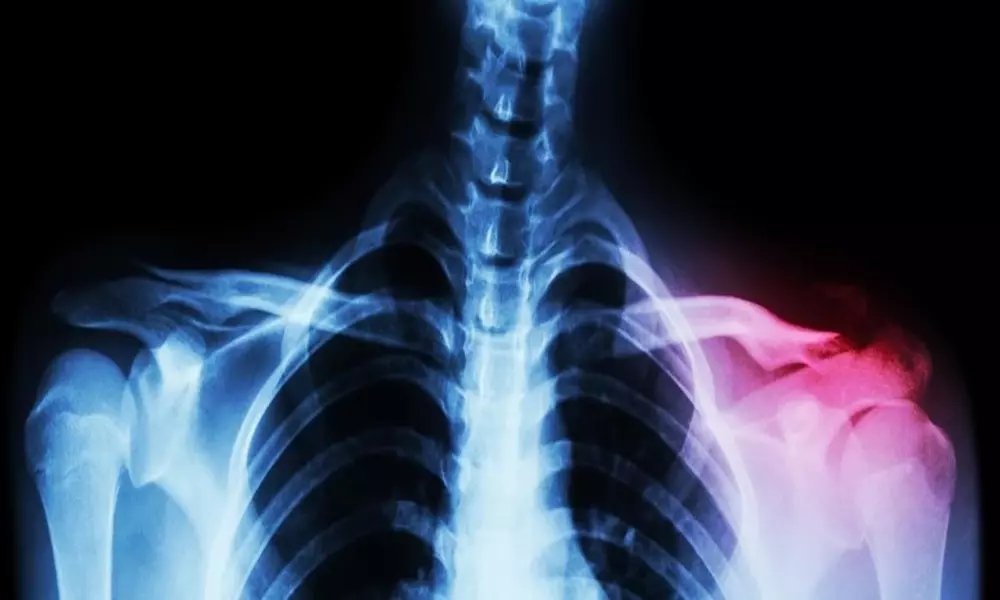

شکستگی ترقوه 7 آذر 1402

• بیماری ها

• مقالات

شکستگی ترقوه: علائم، دلایل، انواع تشخیص و درمان